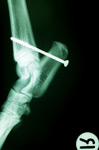

Bone

Bone heals in the same way as any wound and differs only in the maturation phase following the deposition of the granulation tissue bed.

The type of healing which subsequently occurs will depend principally on the degree of stability and immobilisation of the fracture site. An adequately stabilized wound (often achieved with the use of bone plates, external fixateurs or pins will result in the conversion of mesenchymal cells into osteoblasts and bone deposition.

Inadequate stabilization will result in the transformation of mesenchymal cells into chondroblasts and the deposition of fibrocartilage into the fracture site. This will result in a “non-union”. In response to this, the bone ends deposit additional periosteal new bone and a so-called hypertrophic non-union develops.

Sutures used in the repair of tendons are usually non-absorbable and are placed in a pattern which directs the pull of the suture away from a longitudinal orientation. Monofilament suture materials such as nylon, polypropylene and stainless steel are preferred, although the newer longer-lasting monofilament absorbable sutures have been advocated as suitable for tendon repair.

Bunnell sutures aim to distribute the tension over a length of the tendon.

Modified Kessler sutures rely on the circumferential compression of part of the tendon to provide strength.

Additional support for the healing tendon such as splints and trans-articular stabilization devices such as screw and pins can help in the first few weeks to maintain proximity of the tendon ends. Weight bearing too early in the course of healing can result in stretching of the healing tendon and a subsequent loss of support to the affected limb.